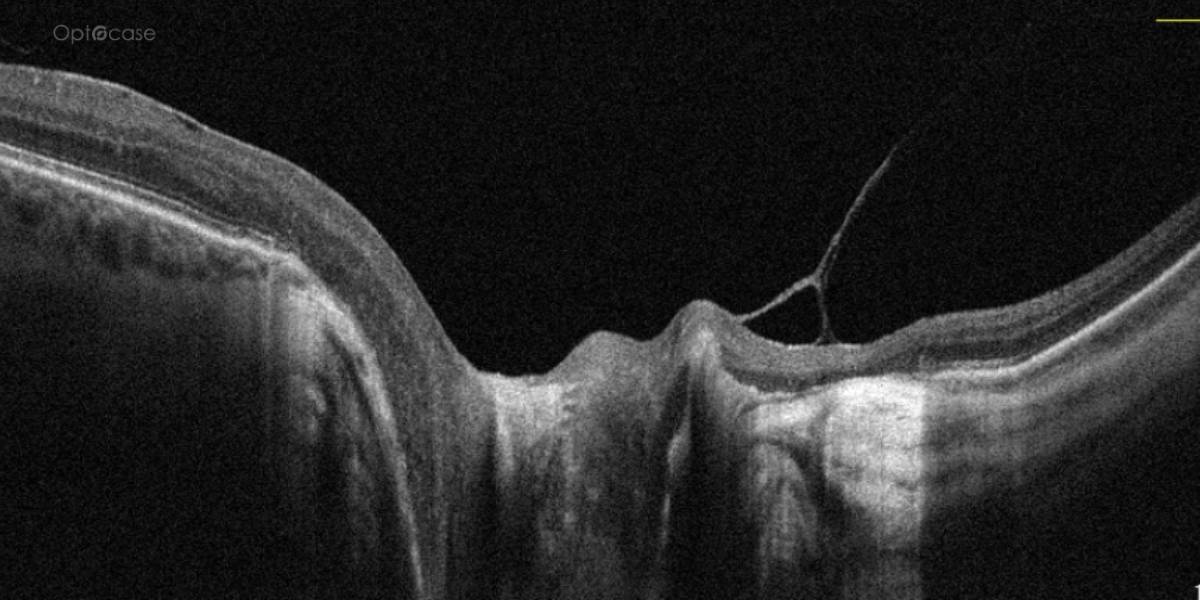

From learn.optocase.com

Disc Hyperreflectivity OPTOCASE Complete Trial Oct Substudy among 4,041 patients randomized in the complete trial, nonculprit lesion stenosis severity was measured using qca in the angiographic core. This oct substudy provides important. — the multivessel immediate versus staged revascularization in acute myocardial infarction (multistars ami). Complete Trial Oct Substudy.